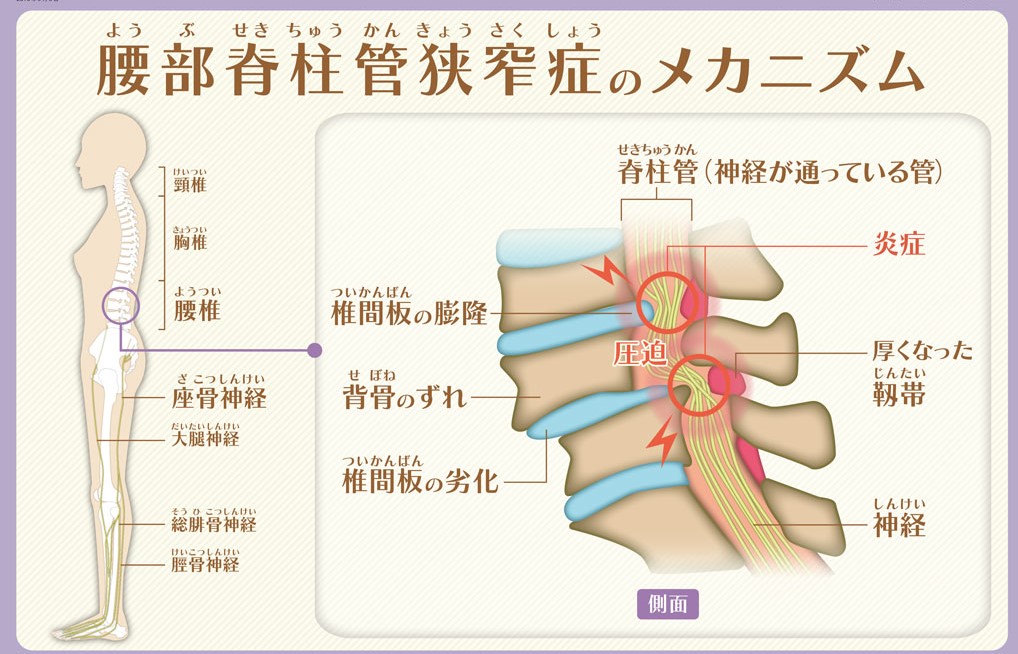

脊柱管狭窄症の原因

脊柱管狭窄症は、背骨のトンネルのような構造をしている脊柱管が加齢等による骨や靭帯の変性や変形により狭くなり、その中を通っている脳から続く脊髄神経が圧迫されることで太ももやふくらはぎに痛みやしびれが出ます。

また、神経の圧迫が強くなって、急激に症状が悪くなり、一定の距離を歩くとふくらはぎ等に痛みやしびれ、疲労感などの症状が現れ歩行が困難になる間欠性跛行の状態になる場合があります。